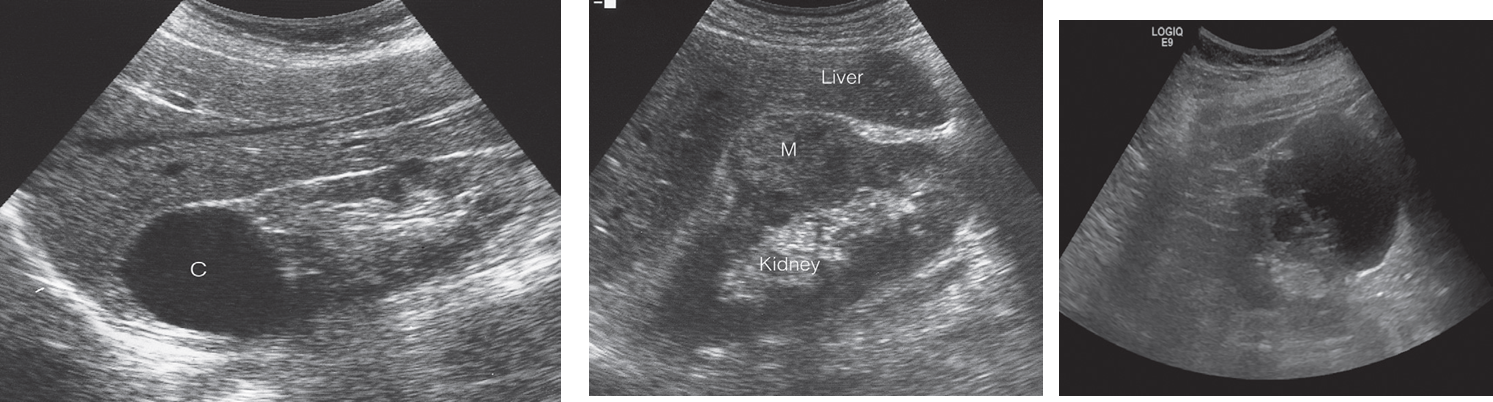

Ultrasound in renal masses.

(a) Simple cyst (C) showing sharp walls and no echoes arising within the cyst. Note the acoustic enhancement behind the cyst.

(b) Tumour showing echoes within a solid mass (M).

(c) Complex cystic mass which could be due to cystic renal cell carcinoma.